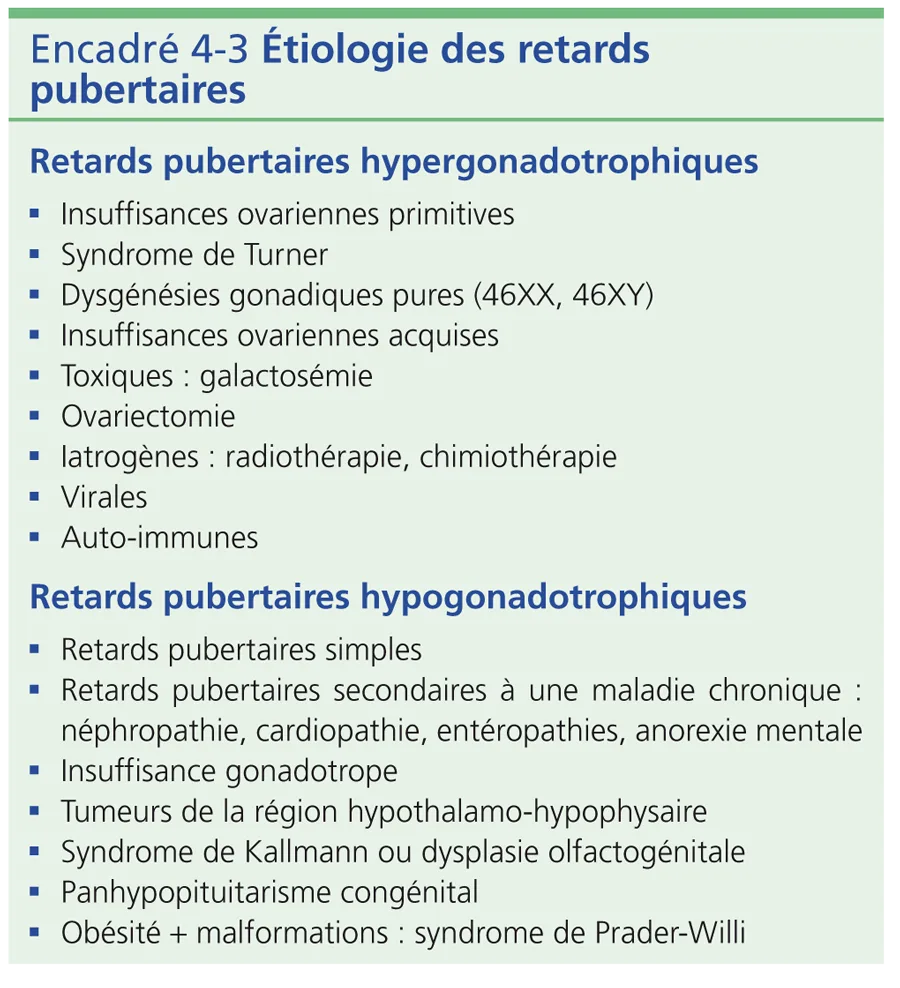

Il n’existe pas de caractère sexuel secondaire. Les données cliniques et le bilan hormonal permettent de distinguer les hypogonadismes hypogonadotrophiques d’origine centrale des hypogonadismes hypergonadotrophiques d’origine ovarienne dont les étiologies sont résumées dans l’encadré 4-3.